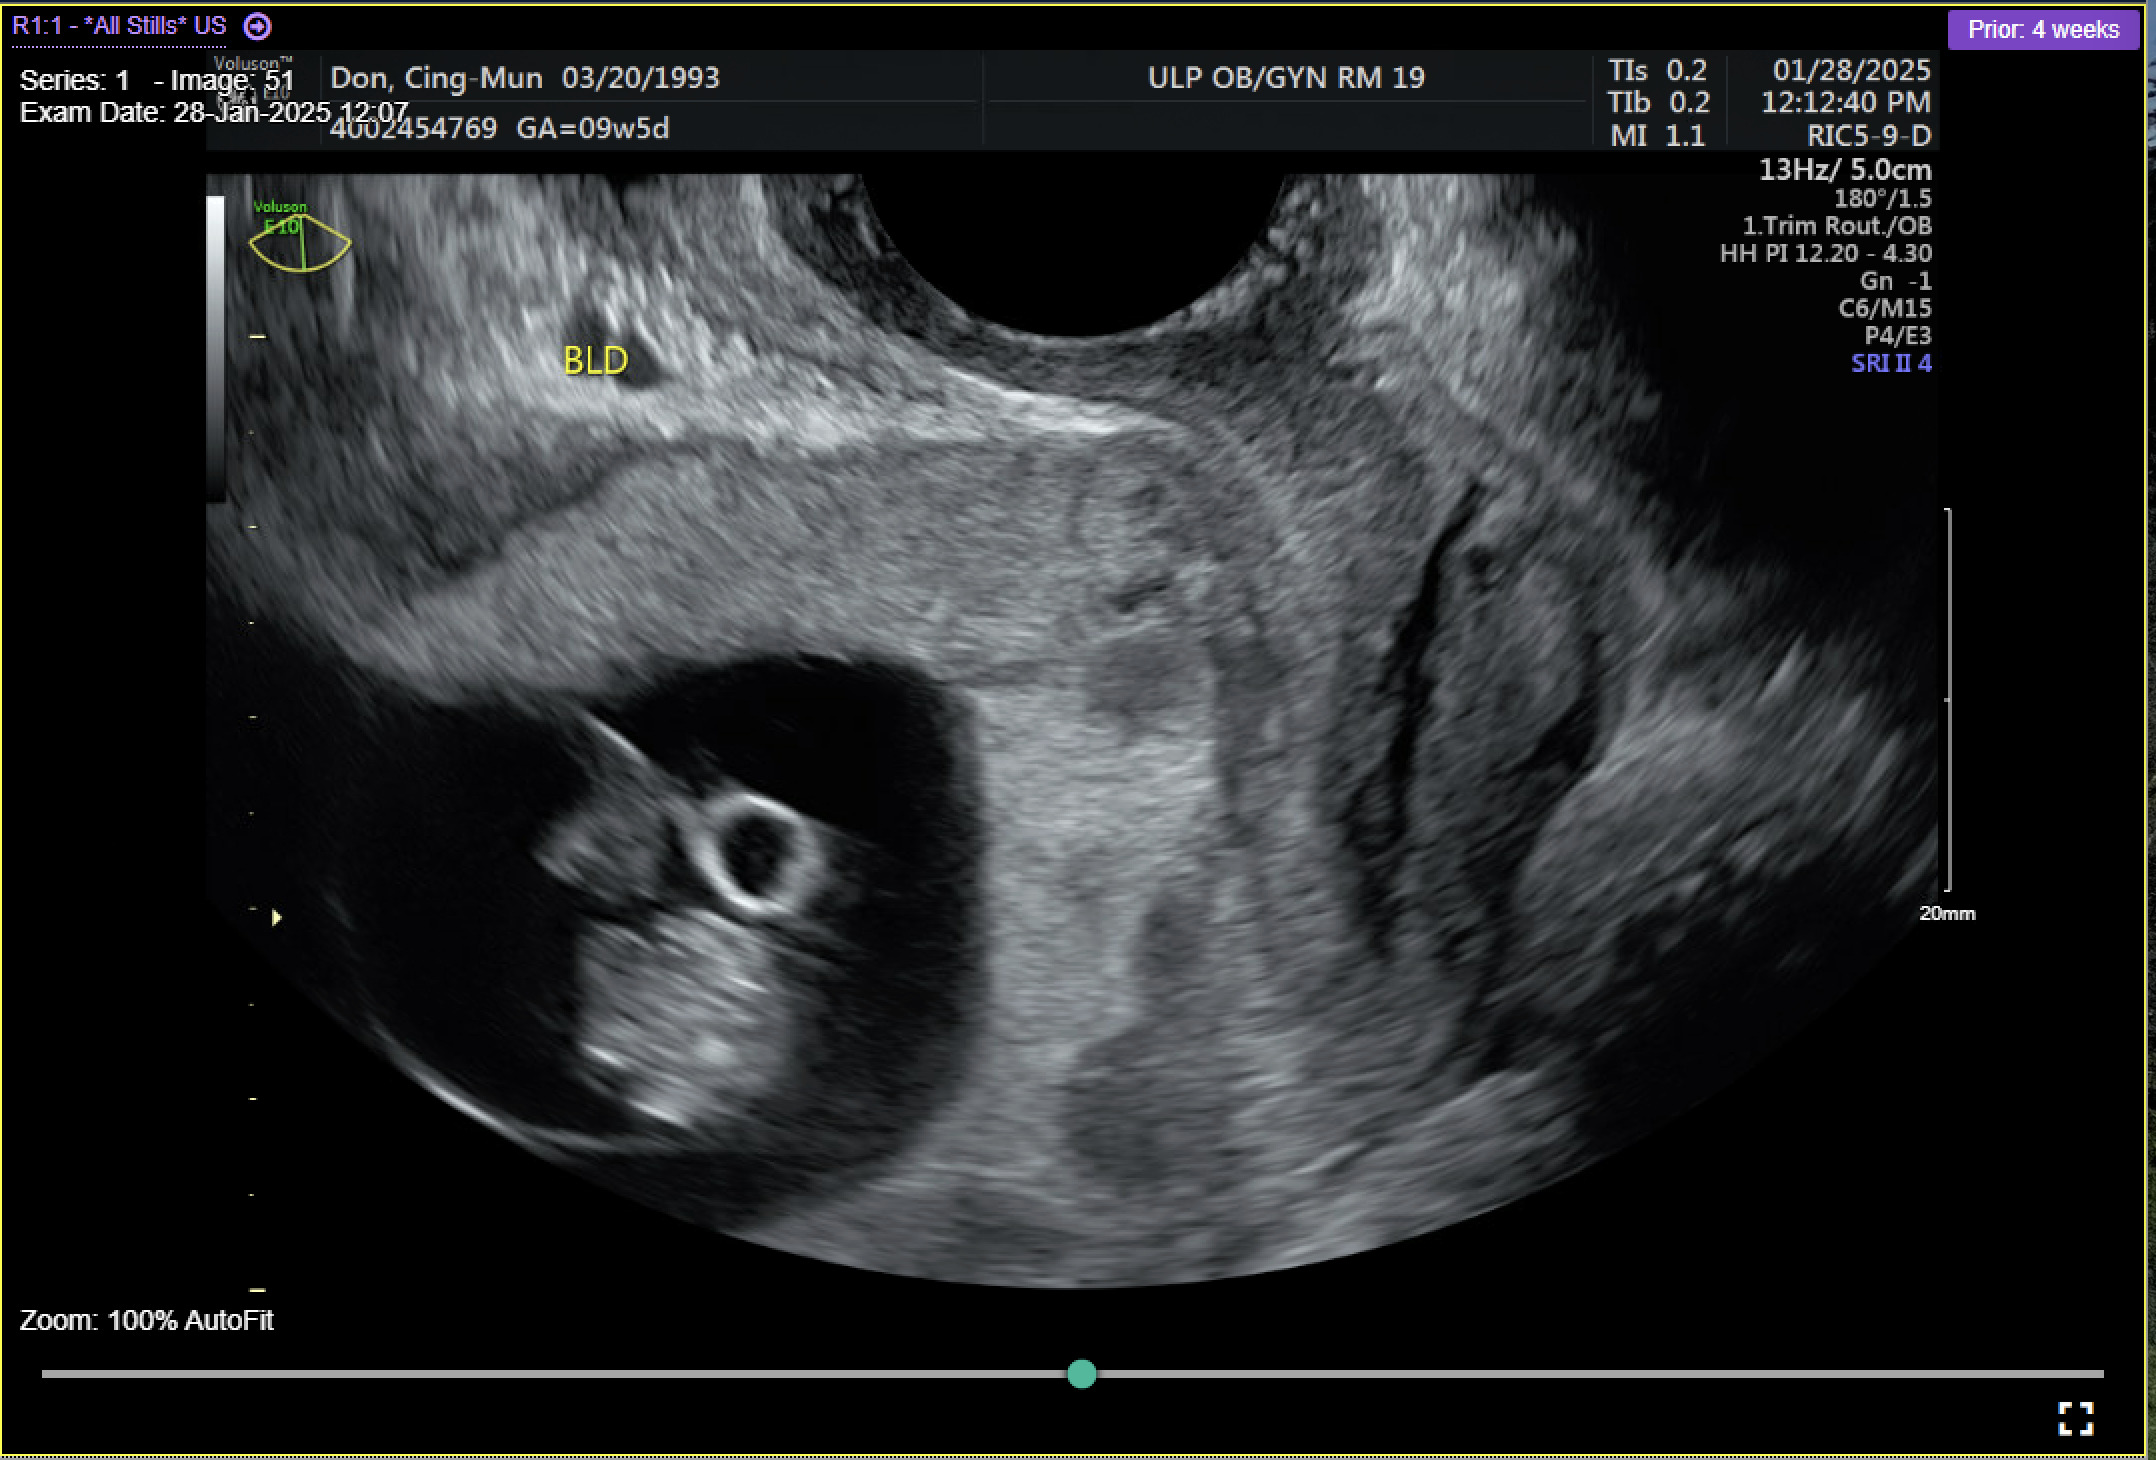

On admission for planned D&C, consents for laminaria placement, suction dilation and curettage under ultrasound guidance, possible uterine artery embolization, and possible hysterectomy were discussed and signed. The patient then underwent successful placement of a large and a medium-sized laminaria without complication. She subsequently underwent suction D&C with ultrasound guidance (Figure 3). Despite the prophylactic placement of 400 micrograms of rectal misoprostol and the administration of 20 units of Pitocin in IV fluids at the start of the case, the patient experienced significant hemorrhage during the procedure with an estimated blood loss of 1500 mL. Intraoperative findings raised concern for uterine rupture (Figure 4). A Foley balloon inflated with 30cc of saline was placed for attempted intrauterine tamponade (Figure 5), and a brisk blood loss of 500 mL immediately filled the foley catheter bag. Vaginal packing and intramuscular methergine were given as additional attempts to control the bleeding, but the patient’s hemodynamic status deteriorated intraoperatively. This necessitated volume resuscitation and transfusion of two units of packed red blood cells. An emergent exploratory laparotomy was then performed to identify the source of the bleeding to repair or perform hysterectomy. A thorough survey of the uterus, adnexa, and adjacent pelvic structures revealed no overt source of bleeding, uterine rupture, or organ invasion with the uterine and bladder serosa intact. No hemoperitoneum was found. Further inspection revealed no additional blood loss beyond the 500 mL blood loss in the foley bag. Blood loss was stabilized, and the patient became hemodynamically stable. The abdomen was closed, and the patient was transferred to interventional radiology for uterine artery embolization, which additionally controlled the hemorrhage. Following embolization, the patient was stable and extubated without issue.